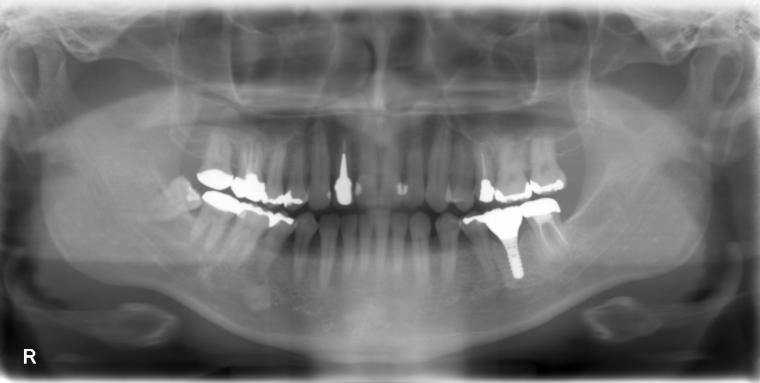

BEFORE

44歳男性

/下顎1本欠損/インプラント埋込手術

他院で左下第一大臼歯を治療していましたが、治療を中断してしまい、状態が悪化、抜歯になった患者さんです。